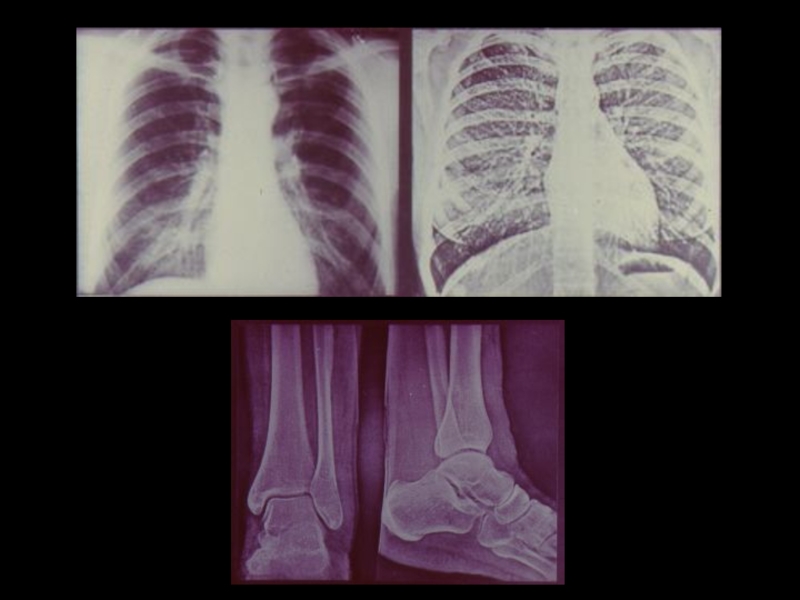

Слайд 64Этапы визуального анализа изображения:

I этап. Общий осмотр изображений

1) Определение

примененной лучевой методики

2) Установление объекта исследования

(части тела, органа)

3) Общая оценка формы , величины, строения и

функции исследуемого органа

II этап. Детальное изучение изображений

1) Разграничение нормы и патологии

2) Выявление и оценка лучевых признаков

заболевания

3) Отнесение суммы обнаруженных признаков к

определенному клиническому синдрому

Этапы визуального анализа изображения:I этап. Общий осмотр изображений 1) Определение примененной лучевой методики 2) Установление объекта исследования

Слайд 65Этапы визуального анализа изображения:

III этап. Разграничение заболеваний, обусловливающих

установленный синдром

IV этап. Сопоставление изображения органа,

полученных при

разных лучевых

исследованиях

V этап. Сопоставление результатов лучевых

исследований с данными других клинических, инструментальных и лабораторных

исследований

(клинико-лучевой анализ и синтез)

VI этап. Формулировка заключения по данным

лучевых исследований

Этапы визуального анализа изображения:III этап. Разграничение заболеваний, обусловливающих 	  установленный синдромIV этап. Сопоставление изображения органа,